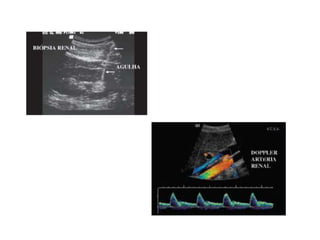

Ultra-sonografia

• Indicações:

 Obstruções do sistema coletor

 Nefrolitíase

 Distinção entre lesões císticas e sólidas

 Avaliação vascular

 Biópsia renal

• Limitações: ar, osso e tecido adiposo.

Ultra-sonografia • Indicações:  Obstruçõesdo sistema coletor  Nefrolitíase  Distinção entre lesões císticas e sólidas  Avaliação vascular  Biópsia renal • Limitações: ar, osso e tecido adiposo.